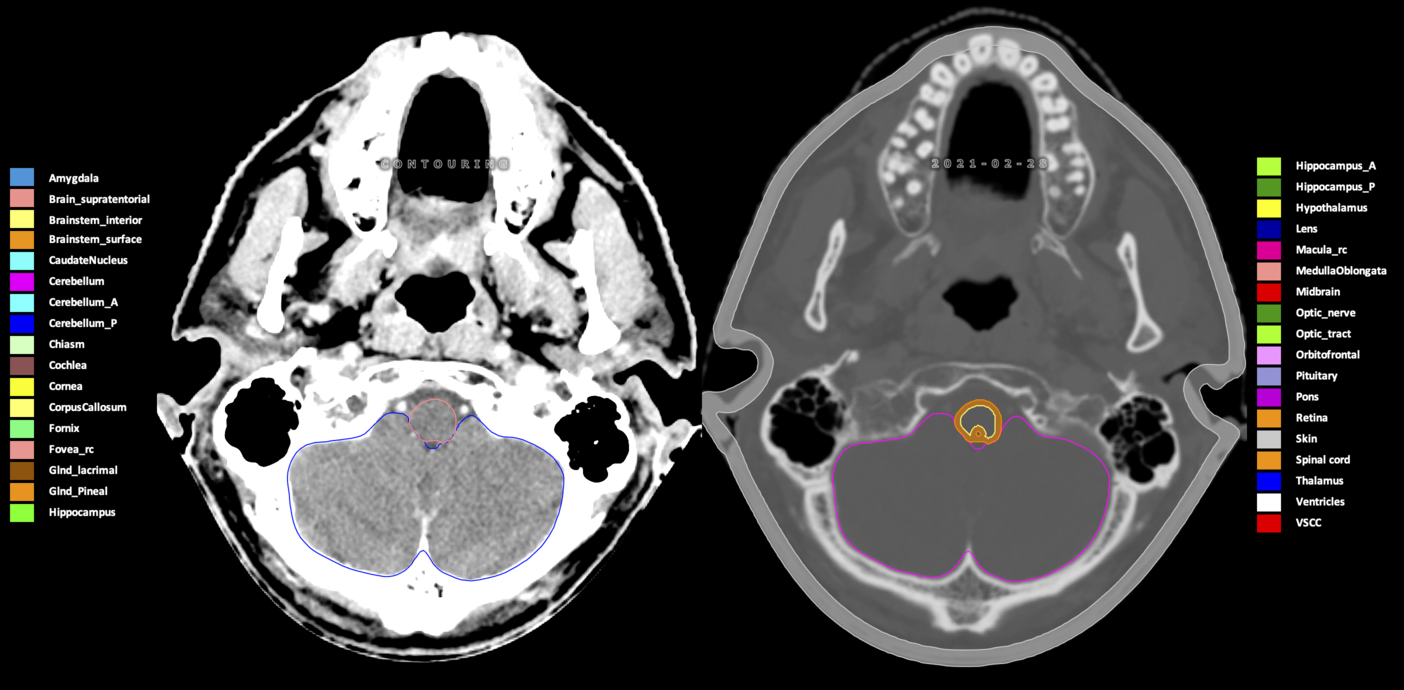

Included are all OARs known to be relevant for radiation-induced toxicity in neuro-oncology: brain, brainstem (midbrain, pons, medulla oblongata), chiasm, cerebellum (anterior & posterior), cochlea, cornea, hippocampus (anterior & posterior), hypothalamus, lens, lacrimal gland, optic nerve, pituitary, skin, and vestibular & semicircular canals. To further facilitate research on cognition, vision and radiological changes after irradiation of the brain, potential clinically-relevant OARs are included: amygdala, caudate nucleus, cerebellum (anterior & posterior), corpus callosum, fornix, macula, optic tract, orbitofrontal cortex, periventricular space (PVS), pineal gland, and thalamus.

Three-dimensional delineation of the 25 consensus OARs for neuro-oncology are shown on CT (WW/WL 120/40, 3000/600), 3T MR images, (T1Gd, T2FLAIR 1mm) and 7T MR (MP2RAGE 0.7 mm). All are presented in transversal, sagittal and coronal view.